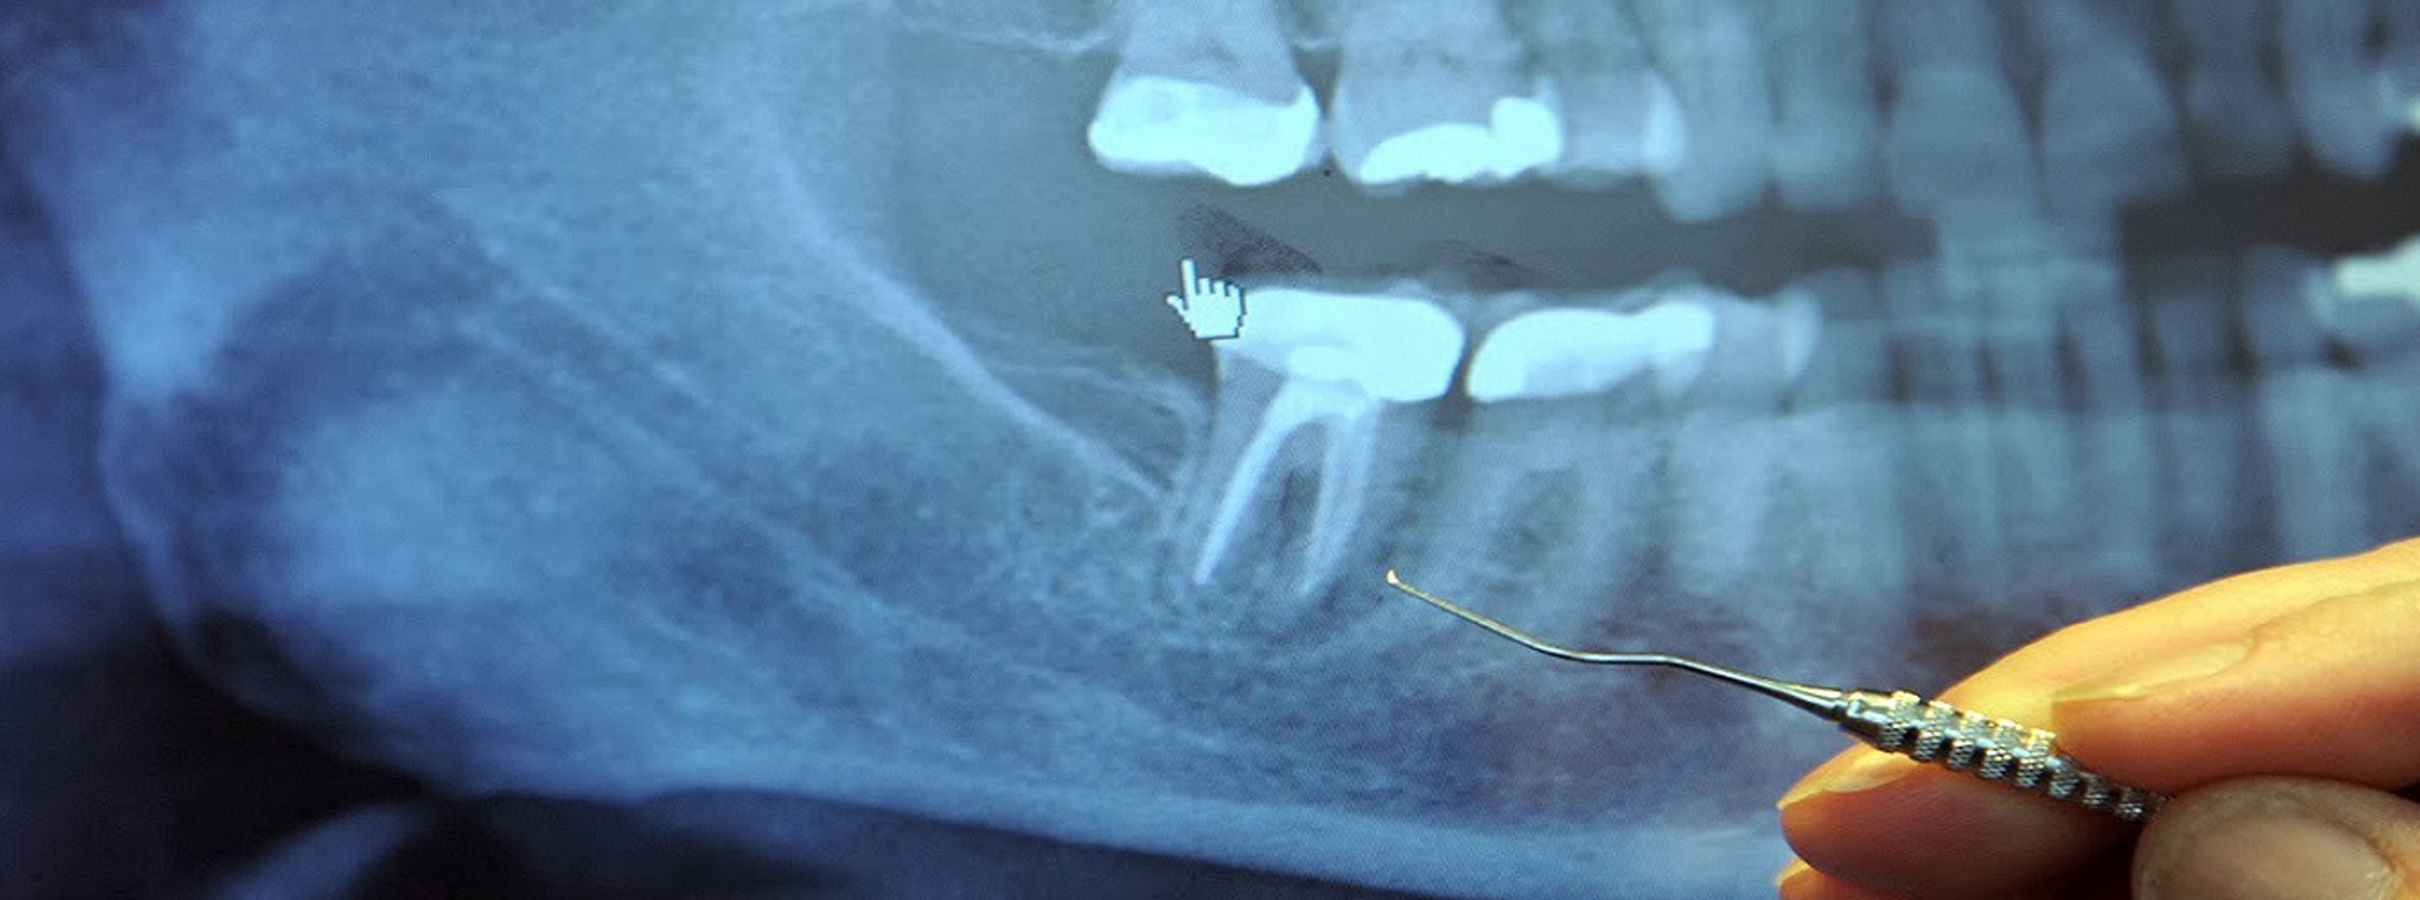

当院では、診断結果を患者さまに説明する際は、レントゲン写真を見せたり、手鏡でお口の中をご自身で見ていただいたりしながら、目で見て分かりやすい解説に努めています。